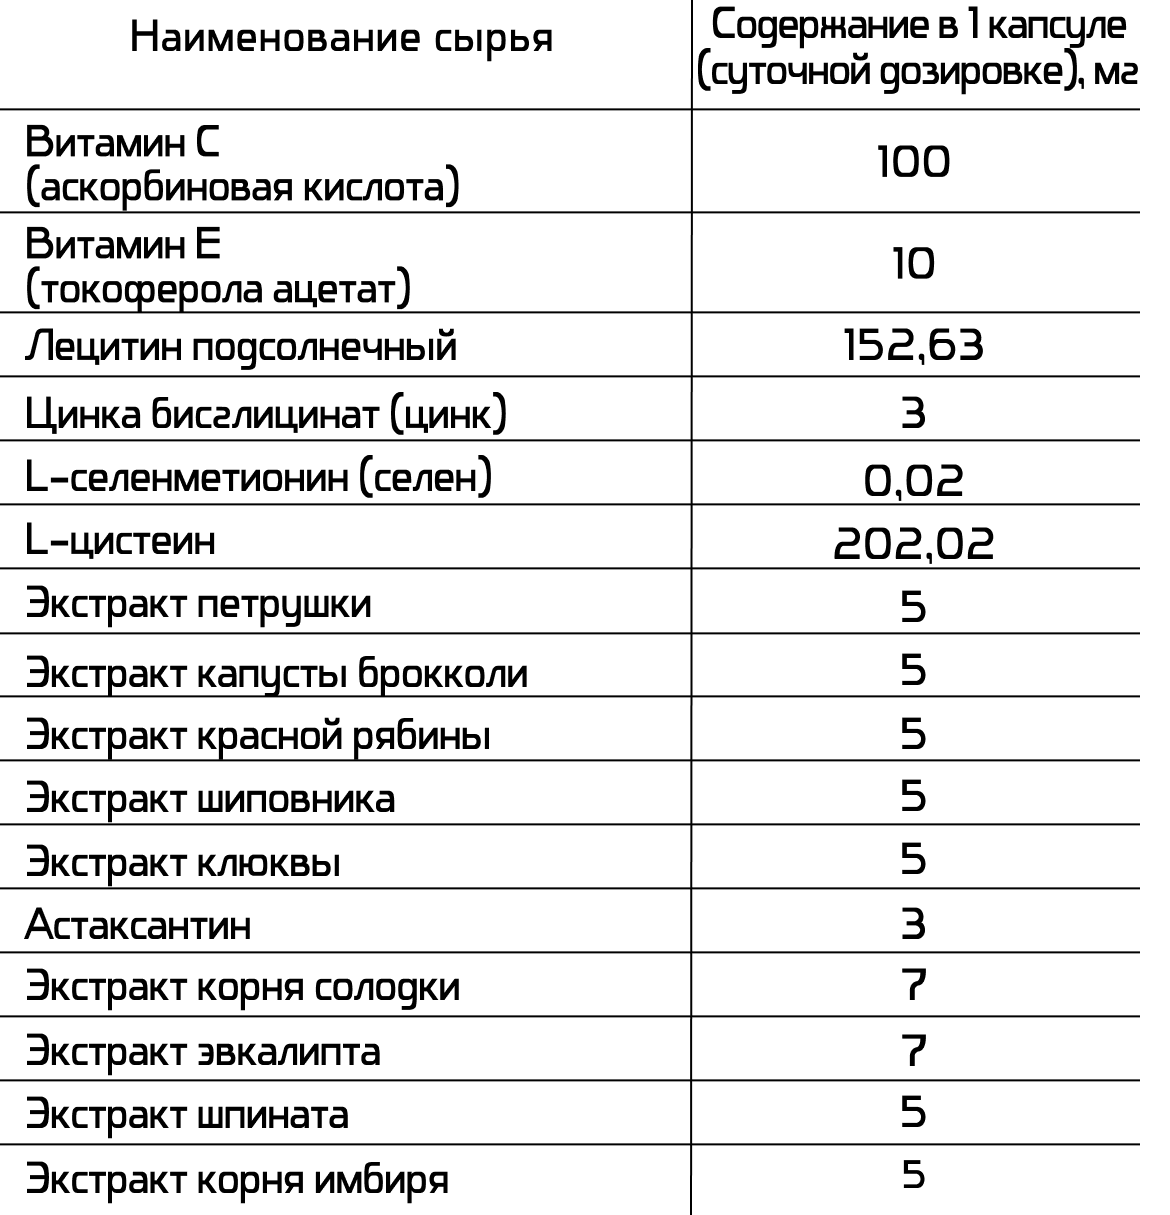

Экстракты эвкалипта и солодки, L-цистеин, астаксантин — способствуют поддержанию комфортного состояния дыхательных путей и нормальной функции дыхательной системы.

L-цистеин, витамины С и Е, L-селенметионин, астаксантин, лецитин подсолнечный, экстракт имбиря, шпинат, брокколи, петрушка — участвуют в антиоксидантной защите организма, способствуют поддержанию естественных процессов очищения.

Витамины С и Е, цинк, L-селенметионин, экстракты шиповника, рябины и клюквы — являются дополнительным источником витаминов, минералов.